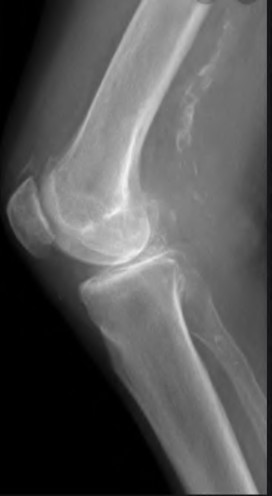

Question 23

A 75-year-old female sustains a fall 5 years after a cementless THA. Radiographs show a periprosthetic femur fracture occurring around the stem tip. Intraoperative assessment reveals the stem remains firmly fixed in the metaphysis, and the proximal bone stock is adequate. According to the Vancouver classification, what is the fracture type and the standard recommended treatment?

Explanation